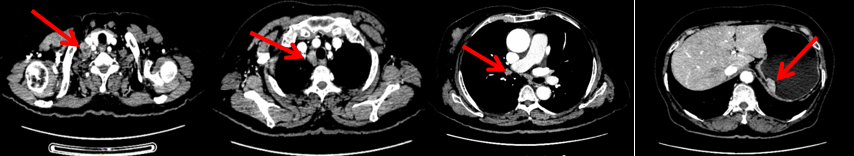

2023.6.26复查PET-CT

1.右乳外上象限乳腺癌病灶(22*16mm),对比2023-04-14 CT(26*24mm)较前缩小,FDG代谢活跃。右侧腋窝小淋巴结(5mm),较前稍缩小,代谢不活跃。右侧锁骨上区、上纵隔淋巴结转移瘤(24*18mm),现大小同前相仿,代谢活跃(SUV:6.7)。

2.现胃贲门部术后改变,术区未见明显异常活性灶。

3.左乳、左侧胶窝术后改变,未见明显异常活性灶。双肺小结节。考虑炎性结节可能,建议复查;双肺门及纵隔另反应性淋巴结。

2024-11-5复查CT:右乳外上象限占位(11mm×9mm),较前明显缩小;上纵隔及右肺门多发淋巴结转移缩小;右锁骨上区淋巴结较前增大。余部位未见肿瘤转移及复发征象。

患者右锁骨上淋巴结较前增大,乳腺病灶明显缩小,针对是否需要进行锁骨上淋巴结及乳腺手术,龚畅教授和曾银朵教授又组织了第三次多学科会诊。

影像科:CT显示右侧锁骨上区病灶增大主要表现为液化坏死改变,考虑为治疗后改变而非肿瘤进展所致。